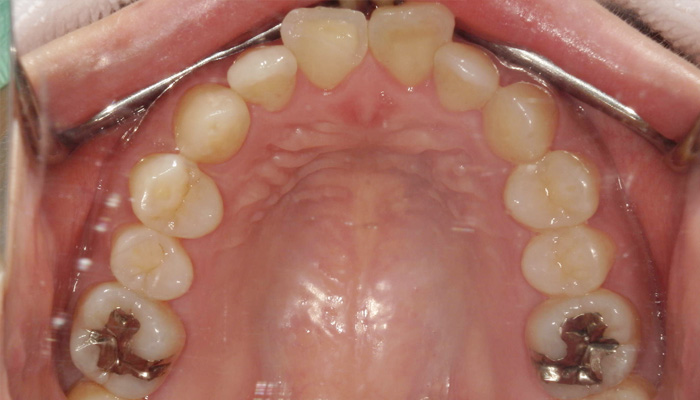

治療後の口腔内写真

術後の口腔内写真

見た目、噛み合せについて、計画通り治療が終了満足していただけました。

マウスピースは再スキャン含めて48枚使用。

光加速矯正装置を使用していたため2年弱かかる予定でしたが1年ほどで終了しました。

インビザラインを行いながらホワイトニングも行い、インビザライン、ホワイトニング終了後に右上の前歯をセラミックにしました。